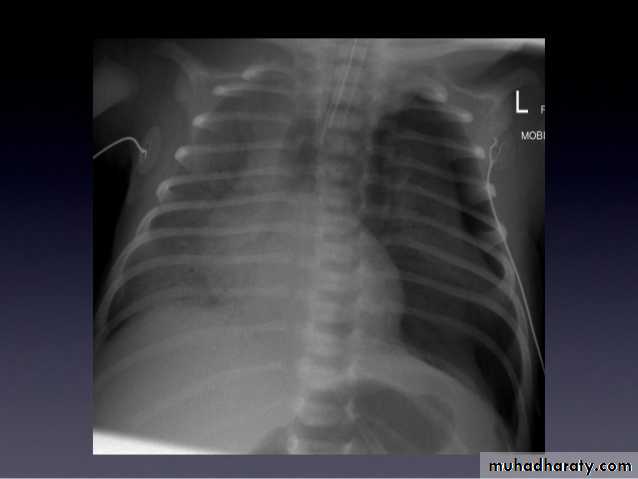

23.normal neonatal chest XR ( normal thymus gland )

24. normal chest XR of the infant( normal thymus gland)